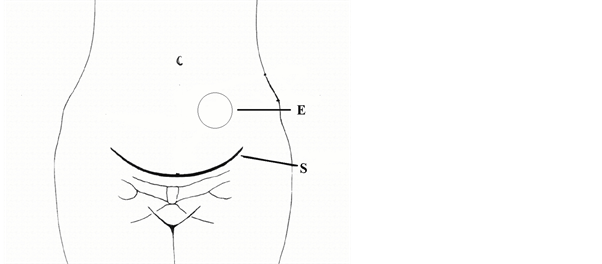

A 36-year-old woman was admitted to our hospital complaining of a mass of the abdominal wall with pain during the menstrual period. The mass was referred to have grown gradually in the past 2 years, with worsening of the intermittent and sometimes severe pain irradiating from the abdominal mass. The patient had two pregnancies in the past, the second of which by caesarean section about 5 years earlier. The caesarean section scar presented in good condition and the mass was not contiguous to the Pfannenstiel’s laparotomy scar, located on the left paramedian epigastric region, a few centimetre above the scar (see Figure 1), rounded, and about 5 cm of diameter, of hard consistence, fixed and adherent to the deep abdominal wall structures. The remainder of the abdominal and gynaecological examinations was unremarkable.

Figure 1. The scheme shows the localization of endometrioma (E) with reference to the Pfannenstiel’s laparotomic scar (S) of the previous caesarean section.